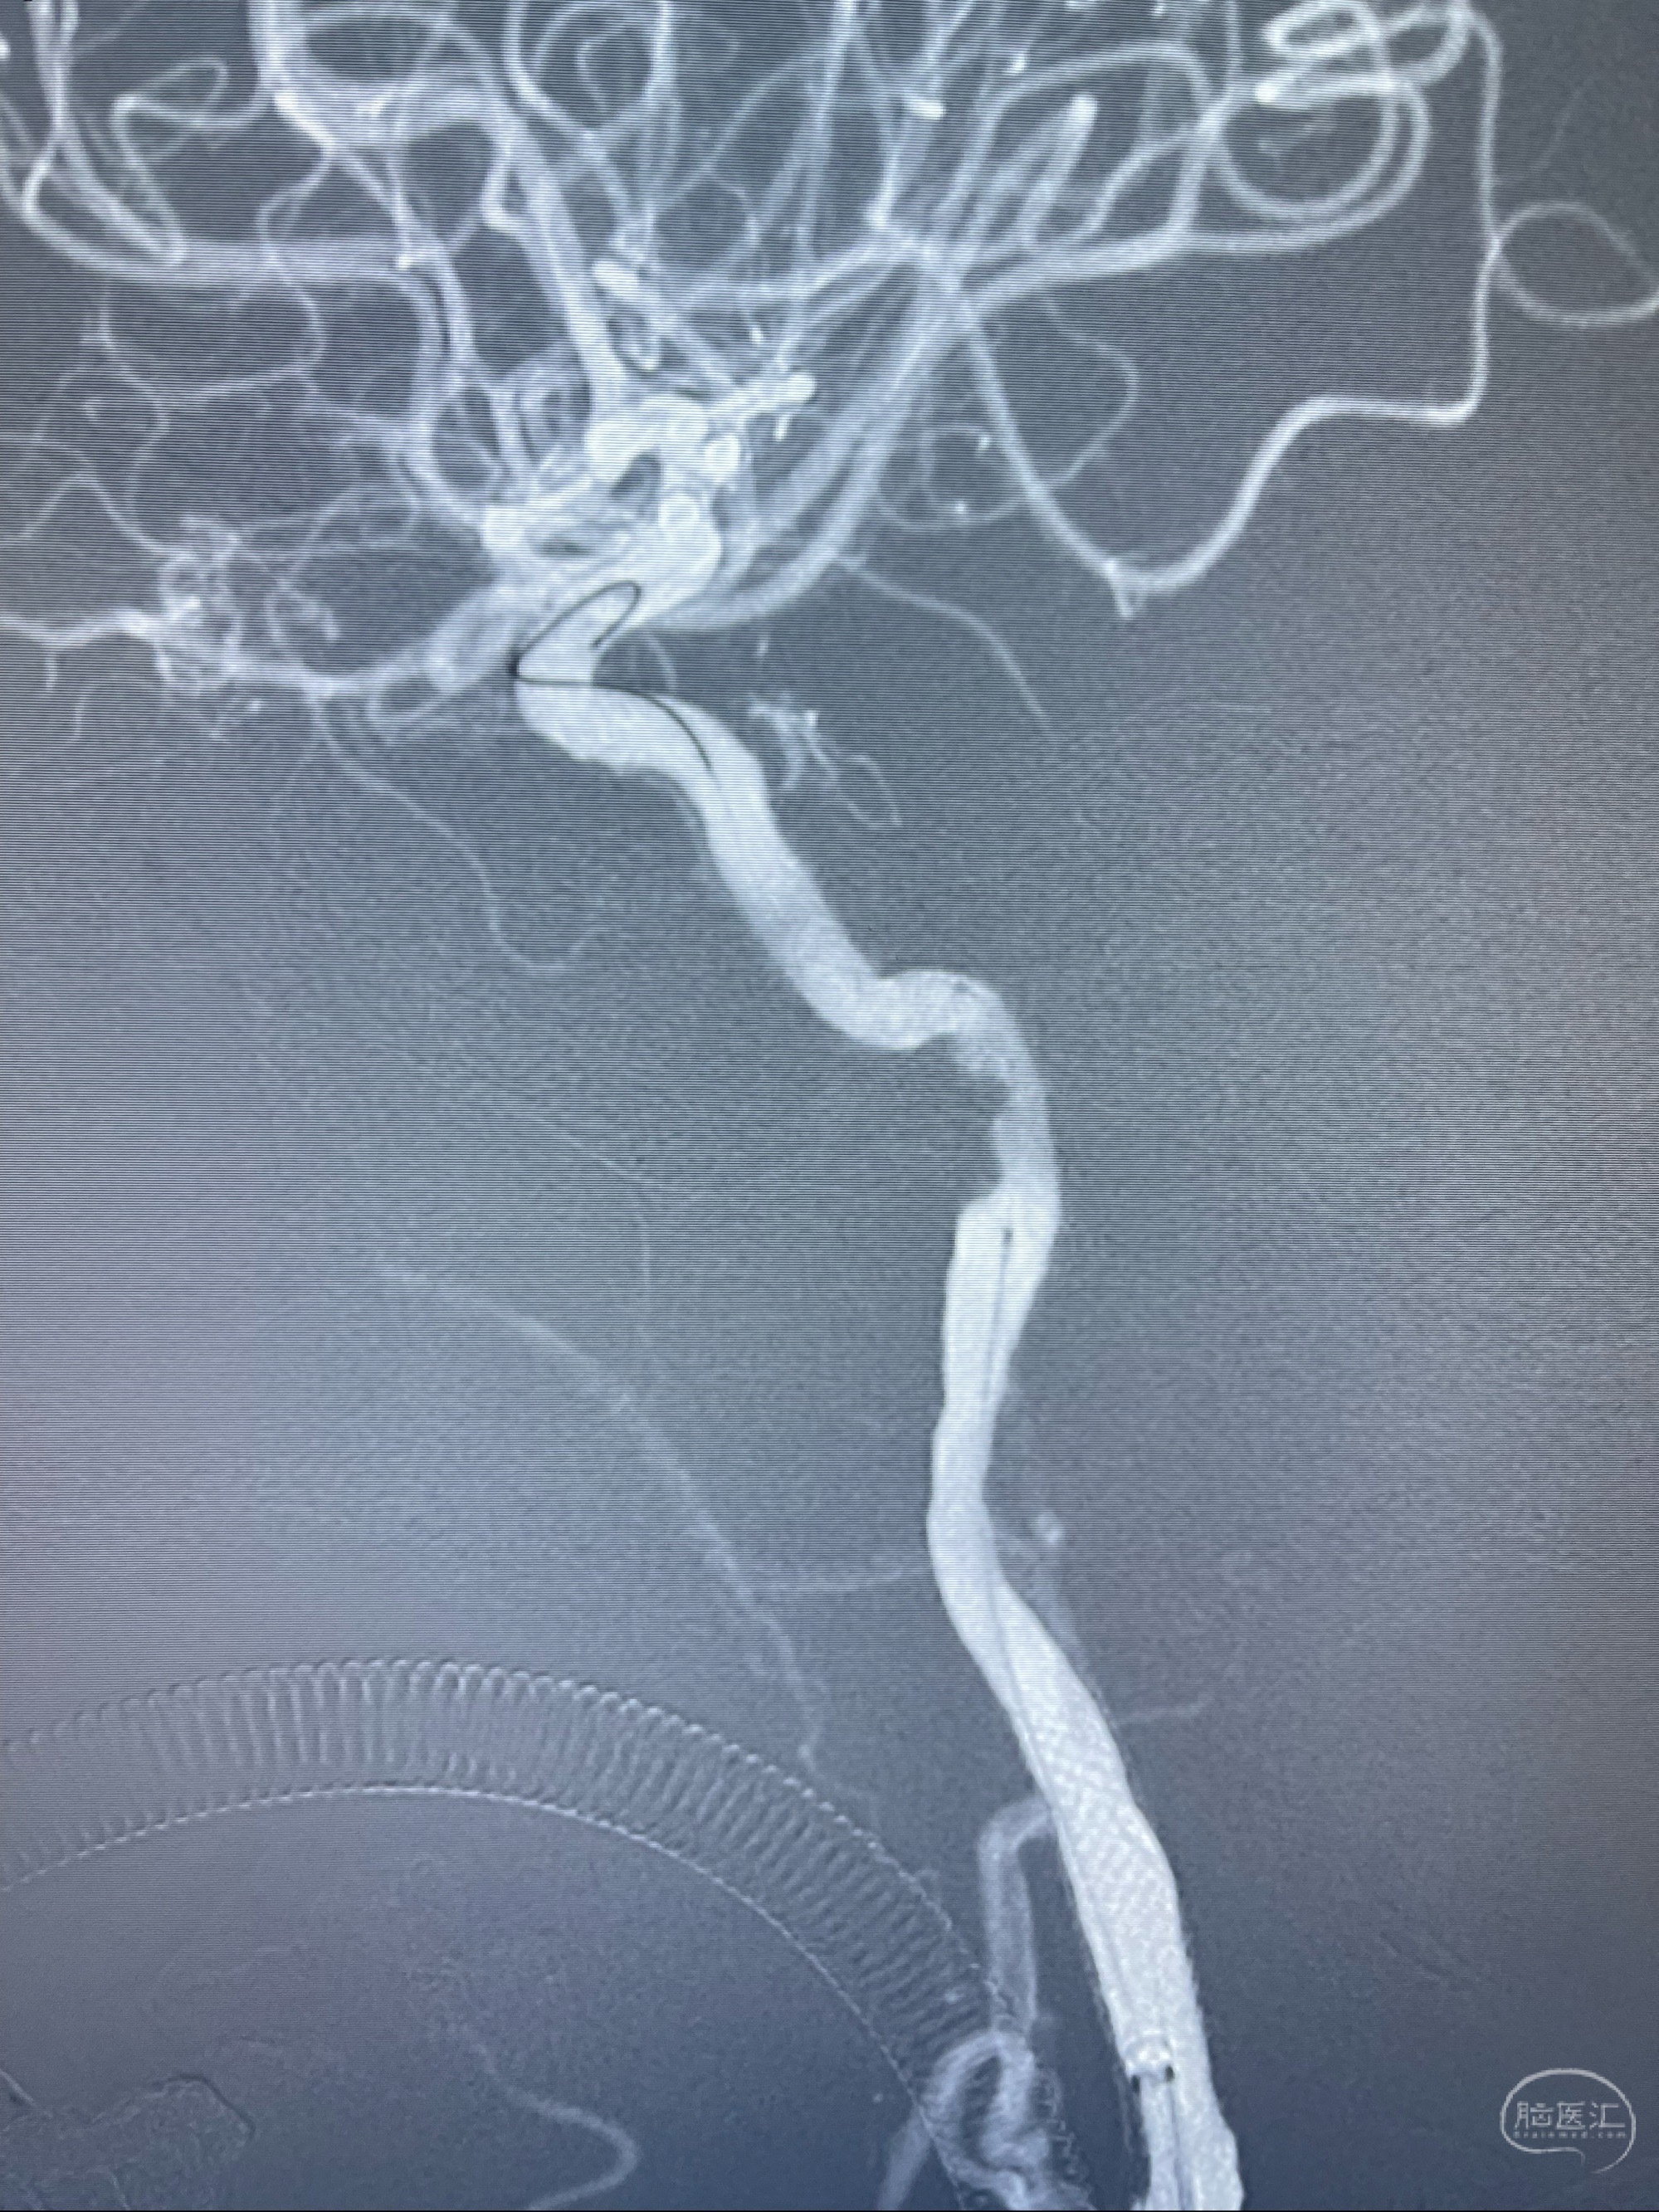

经导引导管造影显示支架远端颈内动脉不规则狭窄伴局部充盈缺损,同时行全身肝素化5ml

泄除球囊造影显示局部管腔扩张佳

即刻造影显示狭窄扩张佳

即刻造影显示支架贴壁佳

支架完全打开,近心端位于原颈动脉支架远心端内